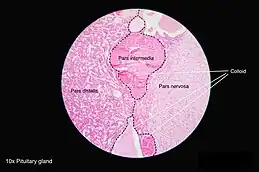

Median sagittal through the hypophysis of an adult monkey. Semidiagrammatic. | |

The pituitary gland is composed of the anterior pituitary lobe, the posterior pituitary lobe, and an intermediate lobe that joins them.[4] The intermediate lobe is avascular and almost absent in humans. In many animals, these three lobes are distinct. The intermediate lobe is present in many animal species, particularly in rodents, mice, and rats, which have been used extensively to study pituitary development and function.[5] In all animals, the fleshy, glandular anterior pituitary is distinct from the neural composition of the posterior pituitary, which is an extension of the hypothalamus.[5]

The anterior lobe of the pituitary can be divided into the pars tuberalis (pars infundibularis) and pars distalis (pars glandularis) that constitutes ~80% of the gland. The pars intermedia (the intermediate lobe) lies between the pars distalis and the pars tuberalis, and is rudimentary in the human, although in other species it is more developed.[5] It develops from a depression in the dorsal wall of the pharynx (stomal part) known as Rathke's pouch.

Intermediate lobe

Although rudimentary in humans (and often considered part of the anterior pituitary), the intermediate lobe located between the anterior and posterior pituitary is important to many animals. For instance, in fish, it is believed to control physiological color change. In adult humans, it is just a thin layer of cells between the anterior and posterior pituitary. The intermediate lobe produces melanocyte-stimulating hormone (MSH), although this function is often (imprecisely) attributed to the anterior pituitary.